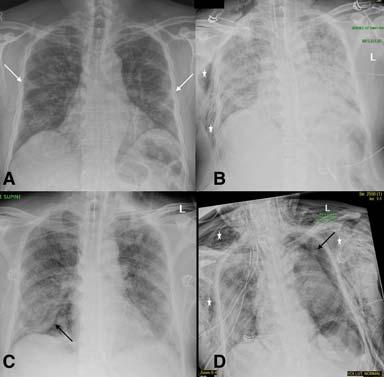

Fig 3 — CXR images from two different patients with COVID-19 showing peripheral areas of consolidation bilaterally in A and unilaterally in B (arrows). Images reproduced with permission from Covid-19 Database of the Societa Italiana di Radiologia Medica e Interventistica.

Fig 5 — CXR’s of different patients with proven COVID-19 demonstrating varied appearances at the time of presentation. ANo abnormalities could be seen on CXR and the corresponding CT (not shown) was also near normal. B- Ill-defined hazy peripheral opacities seen in the left upper zone. C- Multifocal opacities were seen in the right lung on CXR at presentation. D- CXR showing extensive parenchymal infiltrates in a patient who came to the hospital in very bad respiratory distress and was found to have COVID-19 on testing.

Fig 6 — Serial CXR’s of a patient with COVID-19 showing development of atypical findings during the admission. The admission radiograph (A) demonstrates multifocal peripheral opacities (white arrow), followed by the development of right pneumothorax (black arrow) on day 7 (B) of admission with improvement in parenchymal changes subsequently on day 15 of admission (C). He developed extensive left pneumothorax (black arrow) and surgical emphysema (star)(D)of the chest wall later in the course. Images courtesy of Dr Amrita Bajaj, Glenfield Hospital, Leicester.